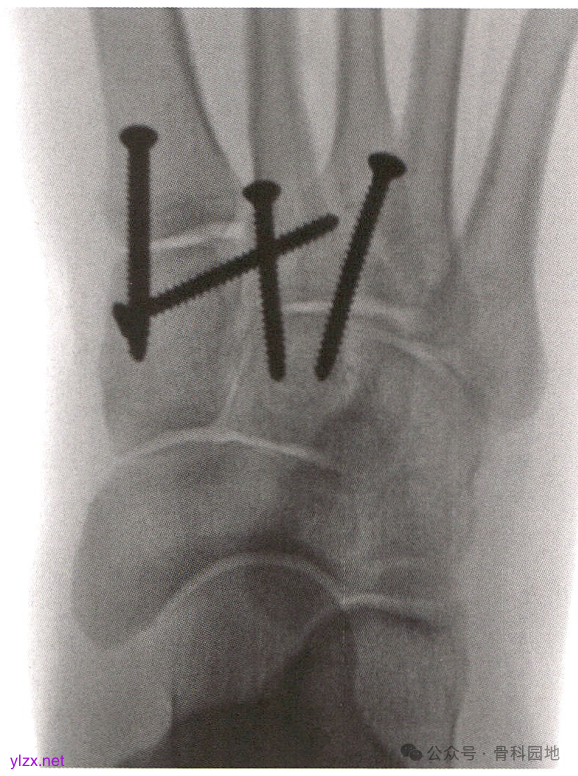

在第1、第2 和第3TMT 关节解剖复位并用克氏针临时固定后,从内侧楔骨向第2MT基底拧入“Lisfranc”螺钉。

完成第1、第2TMT关节的最终固定。

由于4 mm 骨皮质螺钉比 3.5 mm 螺钉或空心钉更坚固且更不易折断,所以建议使用4mm 骨皮质螺钉。但 3.5 mm 螺钉或空心钉对于小体格患者可能是足够的。如果使用空心钉,可以穿过克氏针拧人空心钉;但如果使用实心螺钉,只能从之前固定的克氏针旁边拧人。完成螺钉固定TMT关节,并用C臂机透视确认位置合适后,去除克氏针。